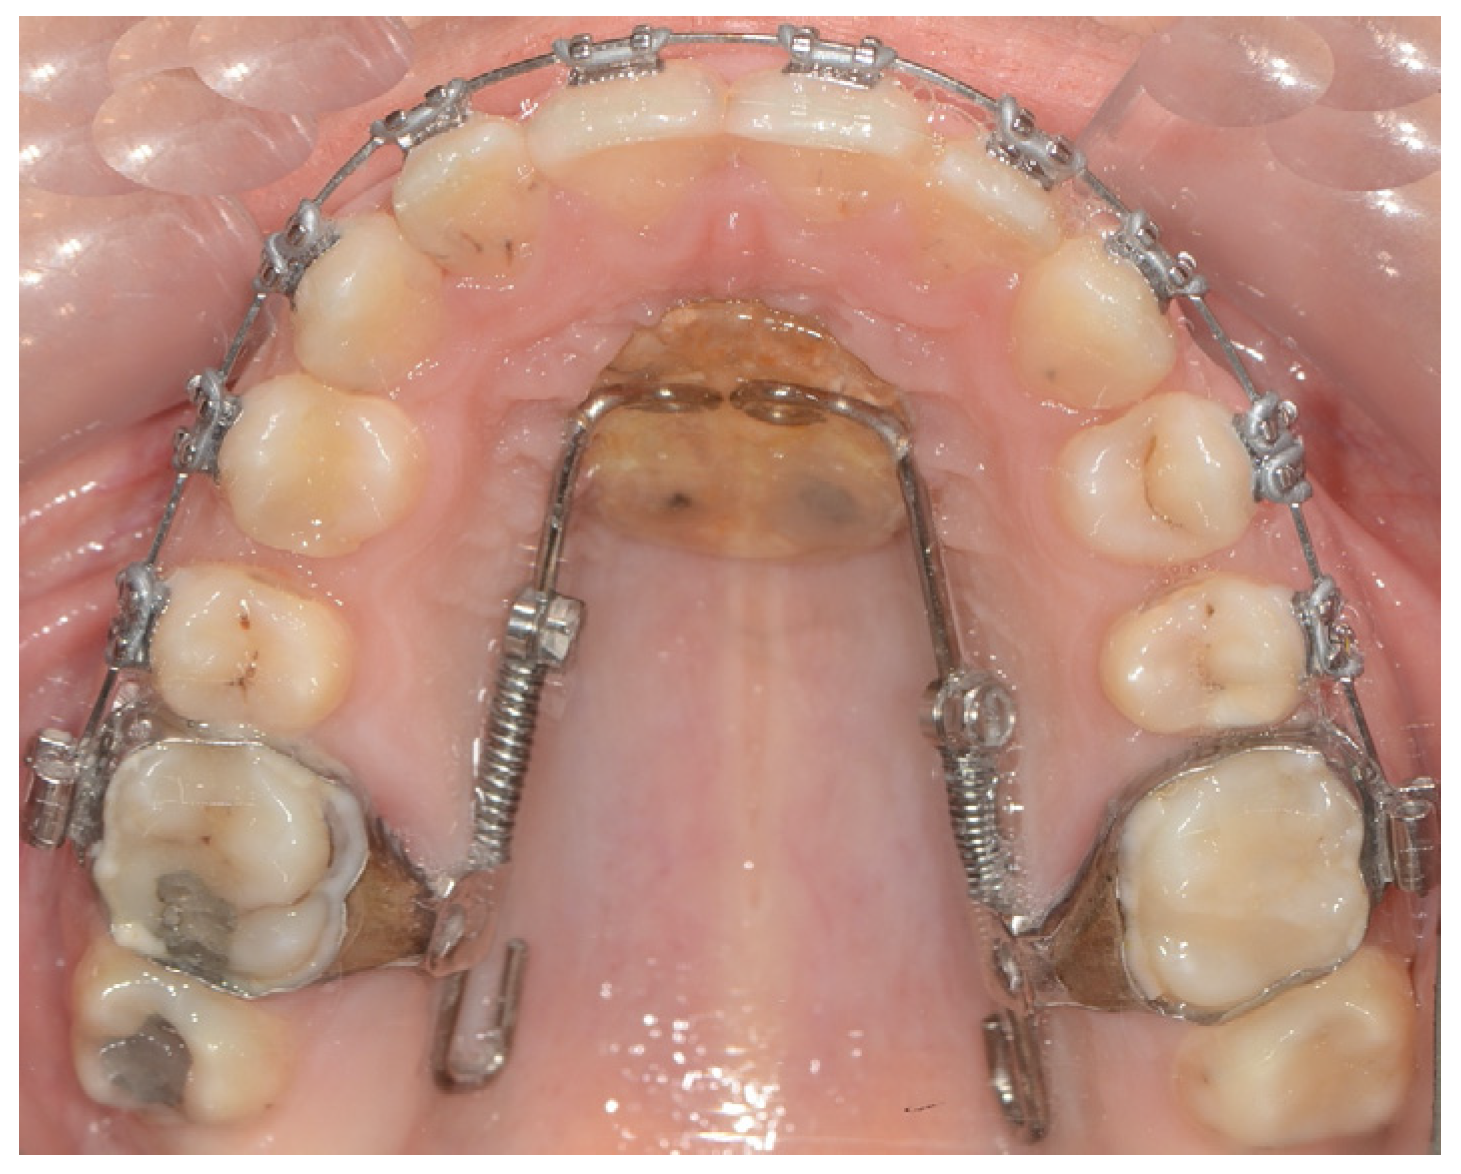

Modified Distal Jet Appliance

| Cozzani et al. (2014) [17] | Skeletal supported (palatinal) | Modified Distal Jet appliance | 4.7 mm distal movement of first molars | 240 g | 9.1 months | No anchorage loss (2.1 mm distalization of upper second premolar) | The modified Distal Jet is a compliance-free distalizing appliance that can be used safely for the correction of Class II malocclusions. |